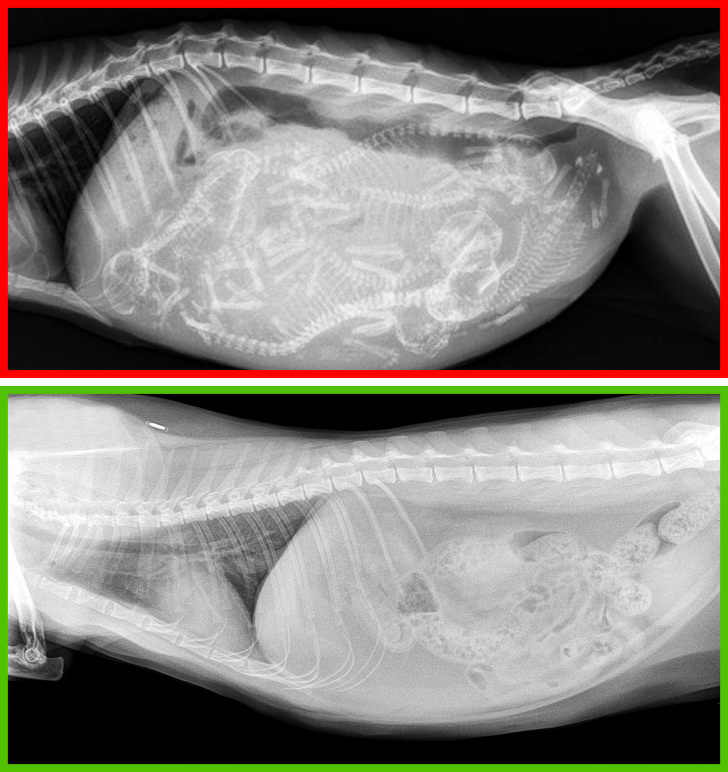

1. Одбивате да направите кастрација или стерилизација на вашата мачка

Слика 1: Рендгенска снимка од бремена мачка

Слика 2: Рендгенска снимка од стерилизирана мачка

Во повеќето случаи, овие постапки имаат позитивно влијание врз здравјето на мачката. Стерилизацијата го намалува ризикот од тумор на градите кај мачките, а кастрацијата го намалува ризикот од тумор на тестисите кај мачорите. Покрај тоа, овие мачки не се склони кон агресија или кон бегање од дома.